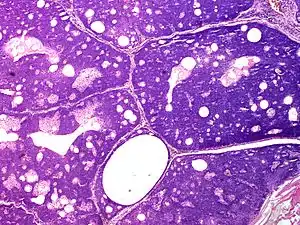

Sebaceoma

Sebaceoma (also known as a "sebaceous epithelioma") is a cutaneous condition that appears as a yellow or orange papule.[1]: 662